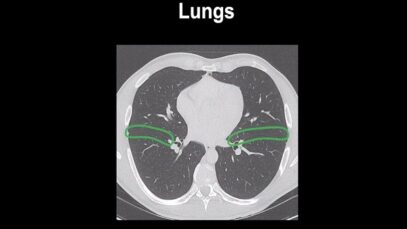

How to identify normal lung anatomy on chest CT

What is CT Scanning of the Chest? Computed tomography, more commonly known as a CT or CAT scan, is a diagnostic medical imaging test. Like traditional x-rays, it produces multiple images or pictures of the inside of the body. A CT scan generates images that can be reformatted in multiple planes. It can even generate […]